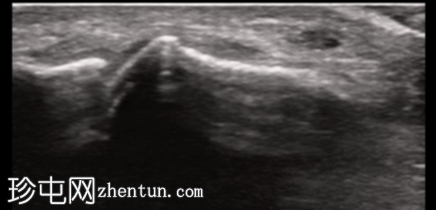

2.png

纵轴切面

第一跖趾关节纵轴切面

关节积液伴轻度滑膜增生。高回声不规则沉积物,符合尿酸钠晶体沉积的典型表现。彩色多普勒成像显示滑膜充血活跃,符合急性炎症活动。